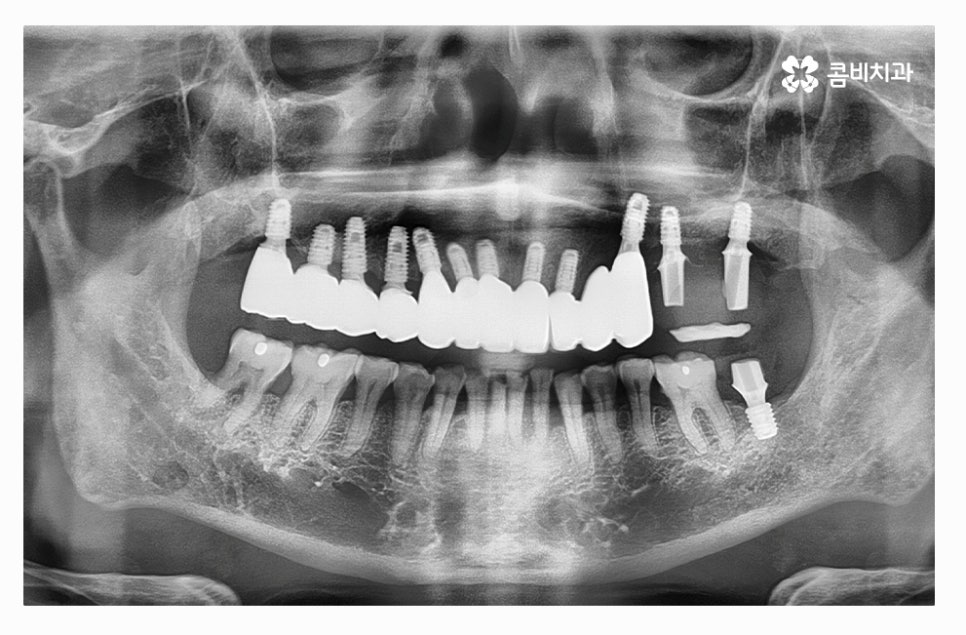

오늘 보여드릴 사례의 경우 치주질환과 염증으로 인해서 윗니를

모두 잃게 되어 전체임플란트 시술을 하게 된 사례라고 할 수 있는데요.

치아를 발치한 후 잇몸 뼈의 상태를 보면 잇몸이 내려앉아 있고

잇몸 뼈가 부족해진 상태라는 것을 알 수 있는데요.

전체임플란트를 해야 할 때 주의사항은 잇몸을 최대한 보존하고

임플란트를 한꺼번에 식립해야 하기 때문에 3D CT 등을 활용한

정밀검진부터 철저하게 해야 하고 식립 각도 하나하나에

철저해야 하기 때문에 의료진의 경험과 실력이 중요한 시술이라 할 수 있어요.